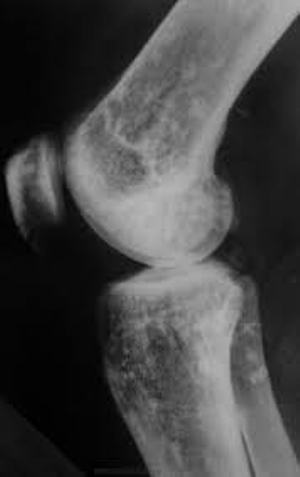

Остеопойкилия — заболевание, основным симптомом которого являются плотные склеротические вкрапления в кости скелета. Они имеют небольшие размеры, как правило — от 2 до 10 мм, и обнаружить их можно на рентгенограмме.

По морфологическим проявлениям можно выделить пятнистую, полосатую и смешанную формы. при этом скелет на рентгенограмме приобретает своеобразный крапчатый окрас. На сегодняшний день известно о 100 достоверных случаях.

Основной метод диагностики – рентгенография. Никаких других дополнительных методов не требуется. На таком снимке видны круглые образования диаметром до 8 мм и более. Иногда вместо округлых включений обнаруживаются полоски, толщина которых может достигать 2 мм, а длина — от 2 до 10 мм. Что же касается смешанных разновидностей, когда у одного человека можно обнаружить и полоски, и круги, то это случается невероятно редко. При этом внешне кости не имеют никаких изменений, окостенение происходит в положенный срок. Также не изменена структура скелетной ткани.